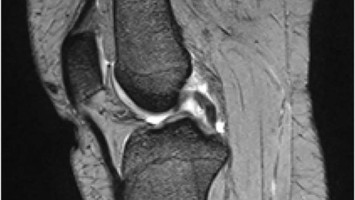

Ungewöhnlicher Kniegelenkschmerz

Eine 17-jährige sportliche Reiterin stellt sich mit innenseitigen Kniegelenkbeschwerden vor, bestehend seid einem Jahr und in den letzten Monaten progredient. Ihr Gangbild war flüssig – doch palpatorisch ließ sich ein isolierter Druckschmerz im Bereich des medialen Kniegelenkspalts auslösen. Was war die Ursache dafür?